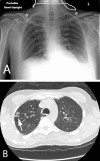

Tuberculous peritonitis is a serious condition with rising prevalence in recent years. It is especially common in those patients with risk factors such as an immunocompromised state, chronic kidney disease, or cirrhosis/liver disease. Spread is typically hematogenous from pulmonary foci. We report on a 34-year-old man who presented with initial complaints of cough, low-grade fevers, abdominal pain, and nausea/vomiting. Chest x-ray showed a cluster of nodular opacities on the right upper lobe, and a CT scan showed diffuse thickening and nodularity of the omentum with prominent mesenteric lymph nodes, consistent with tuberculous peritonitis.